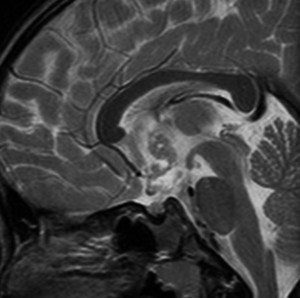

6年以上発ちますが再発はありません。右の画像のように視神経交叉のサイズは正常化しました。下垂体は左に偏っているので,おそらく右側の下垂体にも腫瘍があったのでしょう。汎下垂体機能低下症はありますが,副腎皮質ホルモンの補充は必要なくて,部分的下垂体機能低下症です。この幼児期の低身長が視床下部性であったのか,下垂体前葉機能低下によるものであったのかは不明です。治療後に高ナトリウム血症になる傾向があり,思春期早発症のために成長ホルモンを使用しながらLH-RHアナログを使うという事もしていますから,おそらく視床下部性のGHDであったのでしょう。